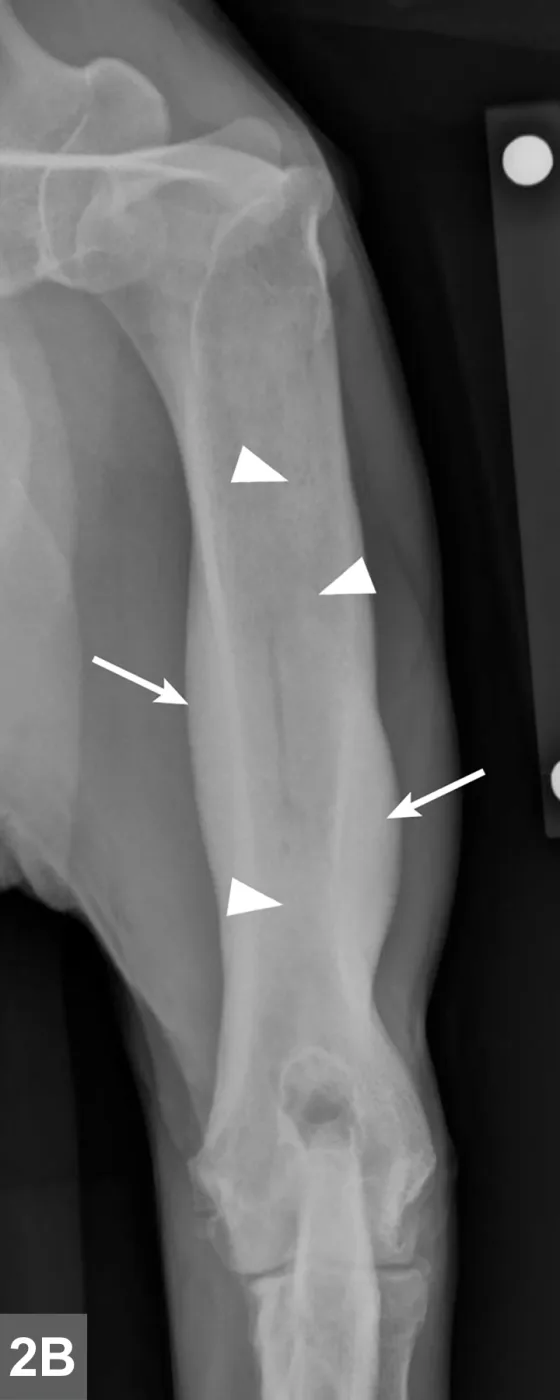

Radiographic signs of panosteitis frequently lag days to weeks behind clinical signs.1,3 The earliest radiographic sign of panosteitis is a decrease in opacity around the nutrient foramen. Later signs include an increase in mineral opacity within the medullary canal of long bones and loss of the normal trabecular bone pattern (Figure 1). Smooth periosteal and endosteal new bone may also be seen in more severe cases (Figure 2). Radiographs of the affected limb may be compared with those of the contralateral limb to assist in diagnosis. Nuclear scintigraphy may assist in diagnosis in cases in which radiographic changes have not yet developed.4

FIGURE 1A

Lateral radiographic projections of the femur (A) and ulna (B, next slide) in dogs with early signs of panosteitis. Note the radiolucency around the nutrient foramen (arrows) and increased opacity within the medullary canal (arrowheads) in both cases.